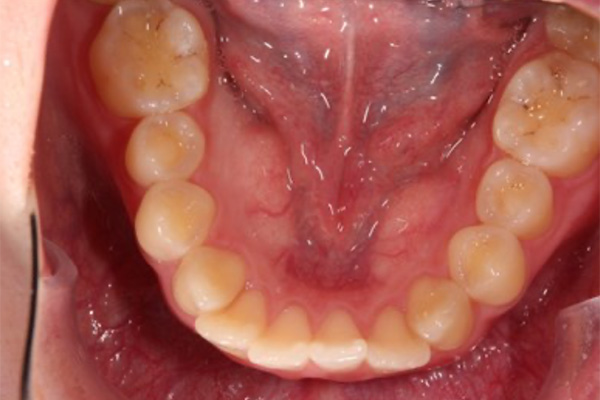

術前

術後